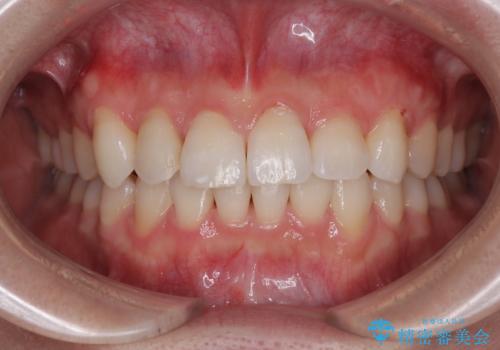

矯正が終わったのでセラミックに変えていきたい オールセラミッククラウン

担当医 有澤哲郎